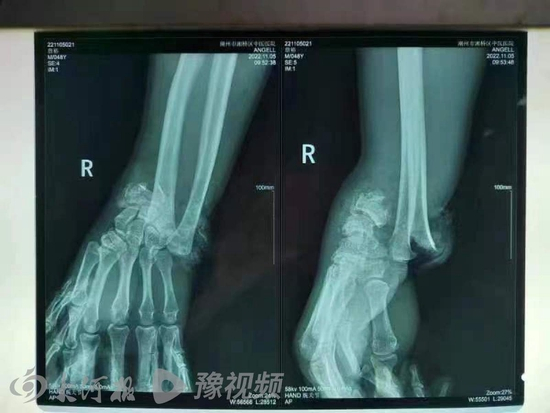

据小詹介绍,事故造成2人身亡3人受伤。3名伤者中,他父亲2根肋骨骨折,腿部受伤;其余2名伤者,一人并无大碍,另一名伤势较重的是骑三轮车的驾驶员,大腿、手等多处部位受伤,需要手术。